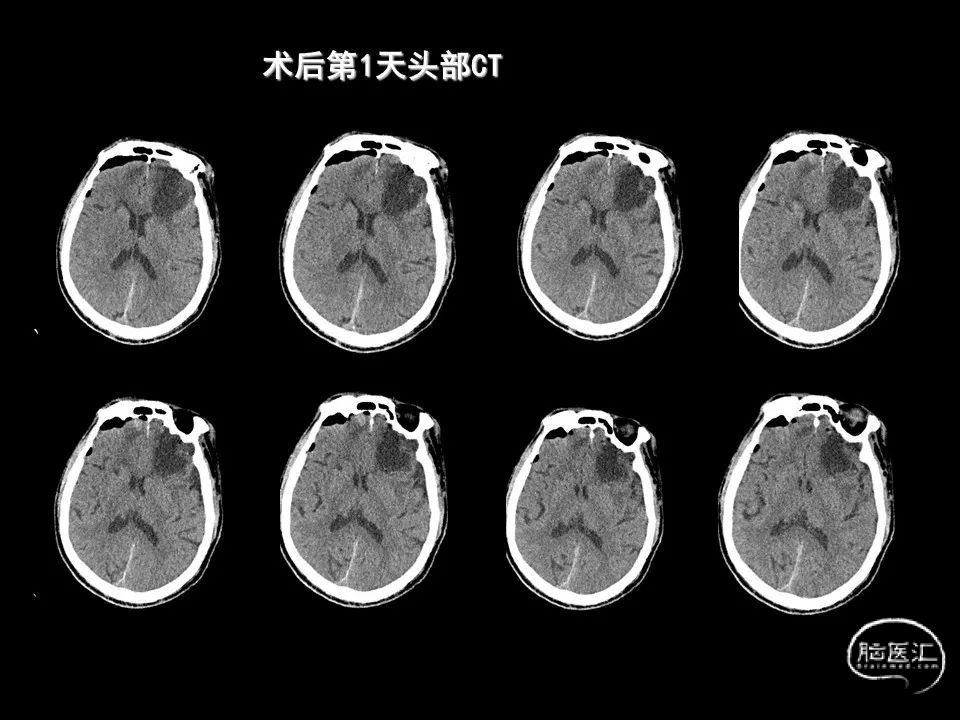

今天为大家分享的是《监测有道丨颅脑创伤-神经重症周刊》第338期,由海南省人民医院朱蔚林教授带来的:2例脑出血微创手术,欢迎阅读、分享。